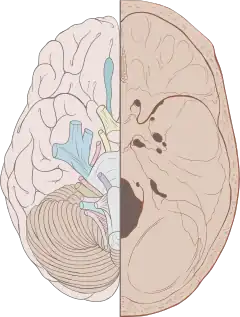

Left View of the human brain from below, showing origins of cranial nerves. Right Juxtaposed skull base with foramina in which many nerves exit the skull. | |

Cranial nerves are the nerves that emerge directly from the brain (including the brainstem), of which there are conventionally considered twelve pairs. Cranial nerves relay information between the brain and parts of the body, primarily to and from regions of the head and neck, including the special senses of vision, taste, smell, and hearing.[1]

The cranial nerves emerge from the central nervous system above the level of the first vertebra of the vertebral column.[2] Each cranial nerve is paired and is present on both sides. There are conventionally twelve pairs of cranial nerves, which are described with Roman numerals I–XII. Some considered there to be thirteen pairs of cranial nerves, including cranial nerve zero. The numbering of the cranial nerves is based on the order in which they emerge from the brain and brainstem, from front to back.[2]

Cranial nerves are numbered based on their position from front to back (rostral-caudal) of their position on the brain,[8] as, when viewing the forebrain and brainstem from below, they are often visible in their numeric order. For example, the olfactory nerves (I) and optic nerves (II) arise from the base of the forebrain, and the other nerves, III to XII, arise from the brainstem.[8]

Cranial nerves have paths within and outside the skull. The paths within the skull are called "intracranial" and the paths outside the skull are called "extracranial". There are many holes in the skull called "foramina" by which the nerves can exit the skull. All cranial nerves are paired, which means they occur on both the right and left sides of the body. The muscle, skin, or additional function supplied by a nerve, on the same side of the body as the side it originates from, is an ipsilateral function. If the function is on the opposite side to the origin of the nerve, this is known as a contralateral function.[9]